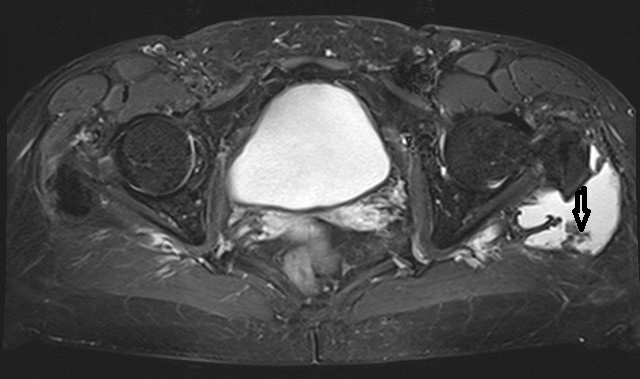

Lateral to the greater trochanter in the bursa trochanterica there was evidence of fluid showing homogeneous hyperintensity without sedimentation in fluid-sensitive sequences. Proton-weighted imaging revealed two nodular wall extensions in teardrop shape extending craniolaterally. These extensions measured a maximum of 1 cm at the base. In addition, at the roof of the fluid-filled cavity there was a space measuring approximately 1.5 x 0.5 cm. In the native fat-suppressed T1 turbospinecho sequence, this space-occupying lesion was partially hyperintense. This was considered to be hemosiderin. After application of gadolinium, there was a vigorous enhancement of the lining of the height. In addition, there was diffuse enhancement of the muscles in the immediate vicinity of the bursa. The hemorrhaged mass showed no enhancement of the contrast medium. In summary, the recent MRI exhibited an enlarged trochanteric bursitis with some intrabursal soft tissue formation suspicious for pigmented villo-nodular synovitis (PVNS) of the bursa trochanteric (PVNSBT) (Figure 1 [Fig. 1], Figure 2 [Fig. 2], Figure 3 [Fig. 3], Figure 4 [Fig. 4]).

Figure 3: T-1 weighted fat-suppressed transversal plane with contrast medium exhibiting the enlargd bursa filled with fluid and soft-tissue protruded into the bursa trochanterica and surrounded by contrast medium (marked by the arrows)